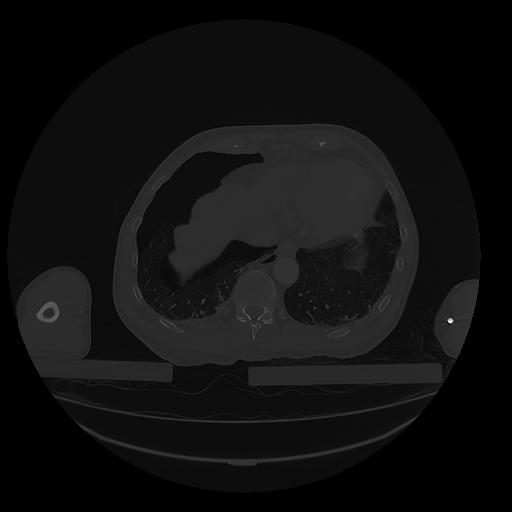

31 PULMON,CE,Vol,1.0,PULMON,,